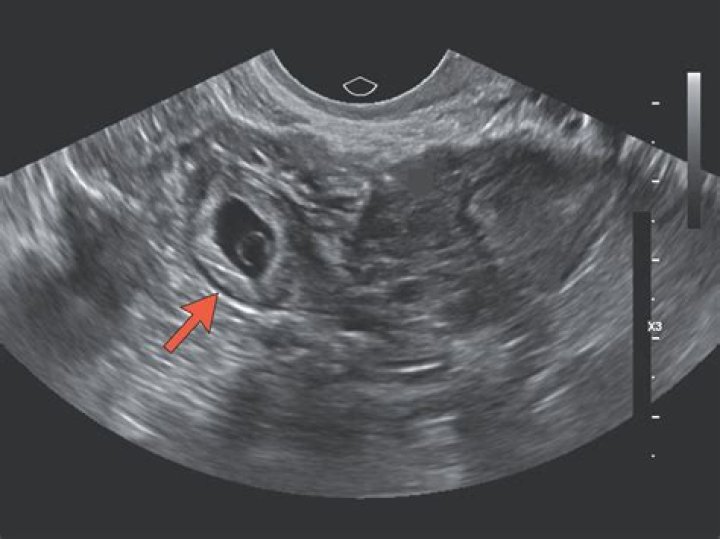

Can ultrasound detect ectopic pregnancy?

An ectopic pregnancy is usually diagnosed by carrying out a transvaginal ultrasound scan.

How Can I Spot an Ectopic Pregnancy With Ultrasound?

An ectopic pregnancy can be suspected if the transvaginal ultrasound examination does not detect an intrauterine gestational sac when the β-hCG level is higher than 1,500 mIU per mL.

Can you see an ectopic pregnancy on ultrasound at 6 weeks?

An intra-uterine pregnancy can usually be seen by 5-6 weeks gestation or when the HCG level is more than 1000 IU/l. In 95% of ectopic pregnancy cases, a good transvaginal ultrasound examination can actually image the ectopic pregnancy in the Fallopian tube.